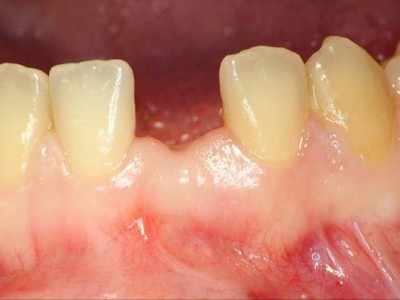

A+ 임플란트의 다양한 케이스를 확인해보세요.